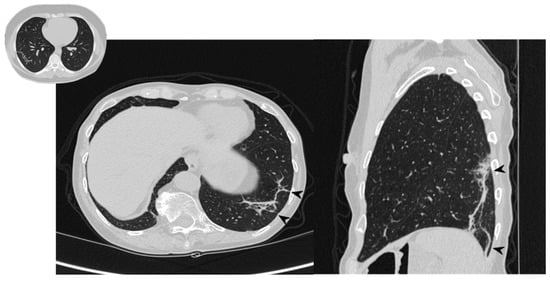

1.4. Perilobular Pattern

The perilobular pattern is characterized by curved or arcade-like bands of parenchymal consolidation with blurred borders and thickening of the interlobular septa—resembling a Roman Arch (Figure 6) [22]. It is a perilobular pattern and often associated with other opacities, especially consolidations [17,24]. The presence of air bronchogram sign helps to differentiate this pattern from atelectasis and fibrotic bands; other conditions that must be excluded are post-primary tuberculosis, lymphomatoid granulomatosis, lymphangitic carcinomatosis, fungal infections, sarcoidosis, pulmonary infarction and interstitial edema [33].

Figure 6. Perilobular pattern: arcade-like bands of parenchymal consolidation (white arrowheads) with blurred borders and thickening of the interlobular septa with a reticular pattern.